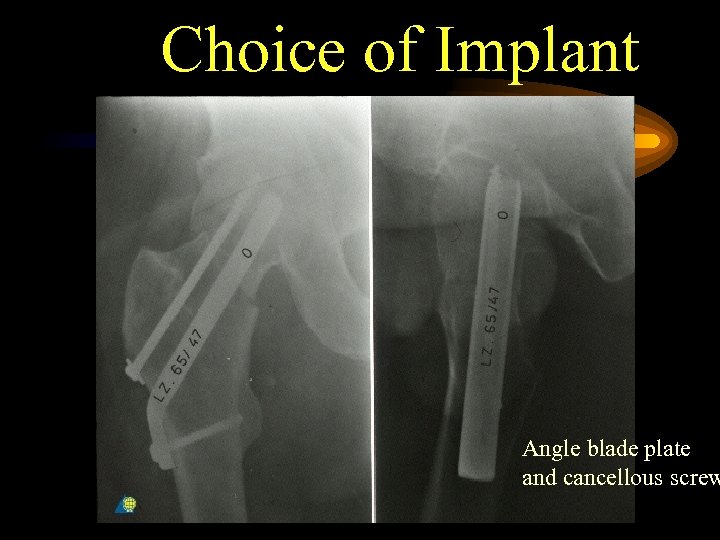

Choice of Implant Angle blade plate and cancellous screw

Choice of Implant Angle blade plate and cancellous screw